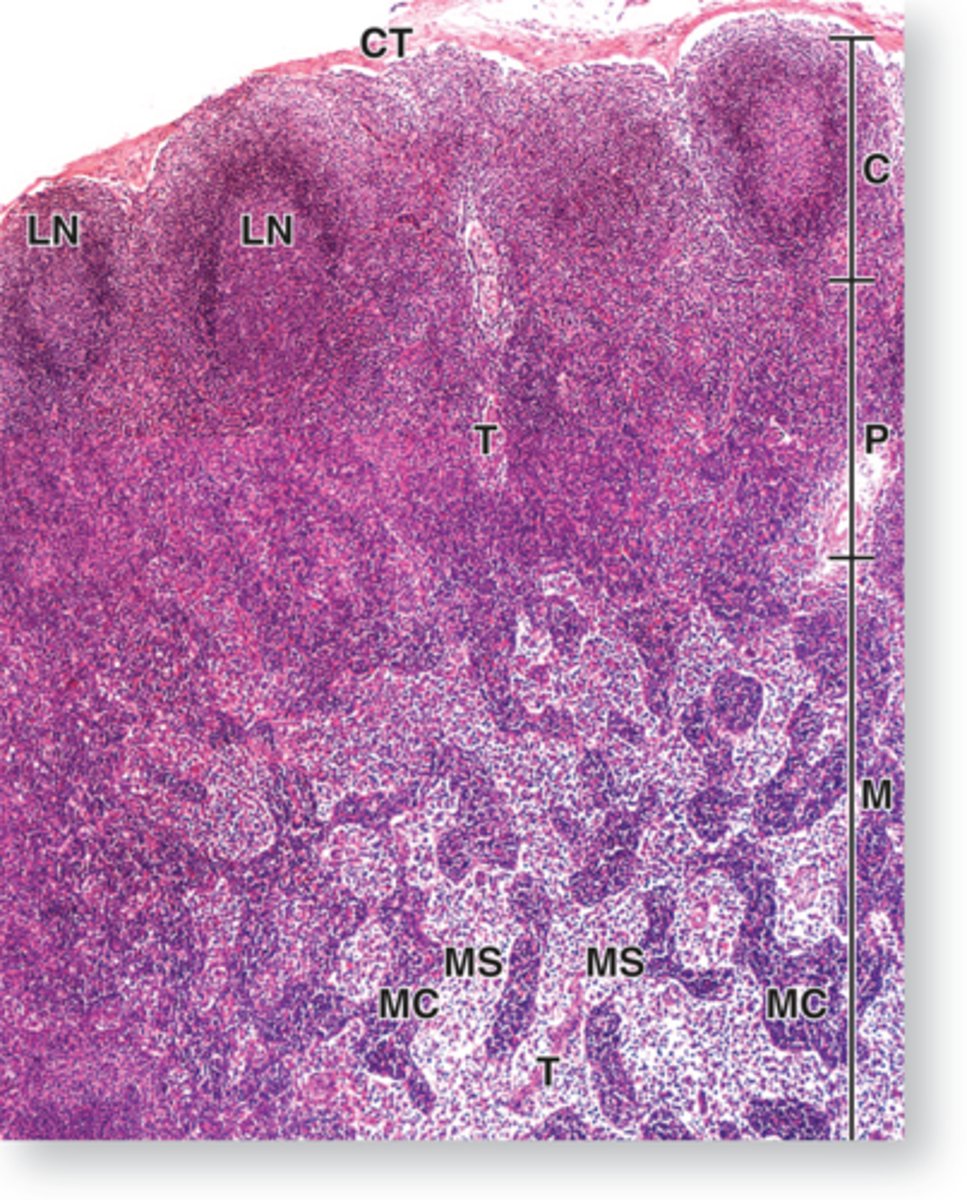

C: cortex

P: paracortex

MC: medullary cord

MS: medullary sinuses

Label the following letters:

MS: medullary sinuses:

Cortex containing B lymphocytes

What is in C?

Medullary cord of medulla contains lymphocytes and plasma cells

What is in MC?

Medullary sinuses of medulla contains macrophages and reticular cells

What is in MS?

lymph node

cortex & paracortex

ID structure

T cells

What is in paracortex of lymph node?

Mostly secondary lymphoid nodules but some primary

What is in cortex of lymph node?